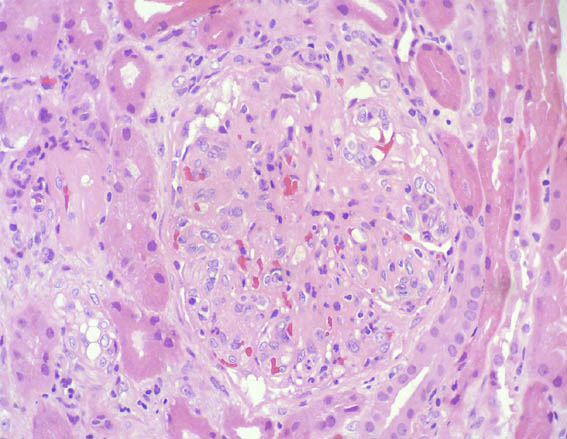

Figure 1.

H&E, X400.